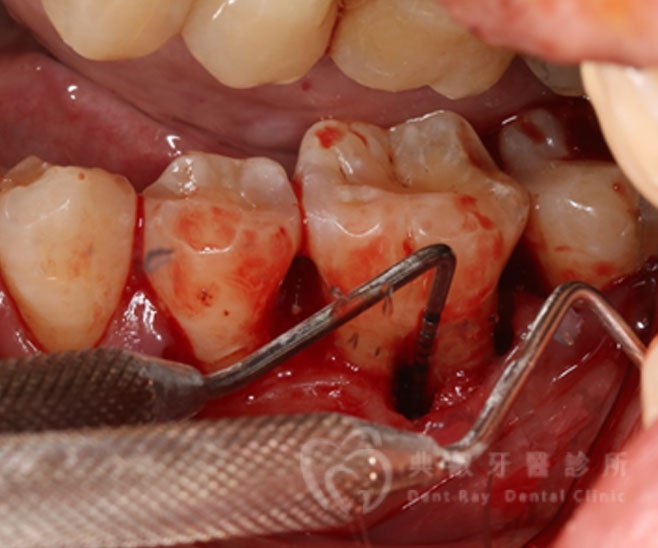

牙周手術案例二

術後兩個月